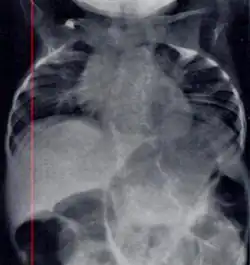

| Radiograph depicting typical skeletal features of Jarcho-Levin syndrome, subtype spondylothoracic dysplasia. Note fanlike configuration of the ribs, with extensive posterior fusion, along with multiple vertebral segmentation defects. | |

Spondylothoracic dysplasia, or STD, has been repeatedly described as an autosomal recessively inherited condition that results in a characteristic fan-like configuration of the ribs with minimal intrinsic rib anomalies. Infants born with this condition typically died early in life due to recurrent respiratory infections and pneumonia due to their restricted thorax.[3][4][5] Recently, a report[6] has documented that actual mortality associated with STD is only about 50%, with many survivors leading healthy, independent lives.

In contrast to STD, the subtype spondylocostal dysostosis, or SCD features intrinsic rib anomalies, in addition to vertebral anomalies. Intrinsic rib anomalies include defects such as bifurcation, broadening and fusion that are not directly related to the vertebral anomalies (such as in STD, where extensive posterior rib fusion occurs due to segmentation defects and extreme shortening of the thoracic vertebral column).[6] In both subtypes, the pulmonary restriction may result in pulmonary hypertension, and have other potential cardiac implications.[7]